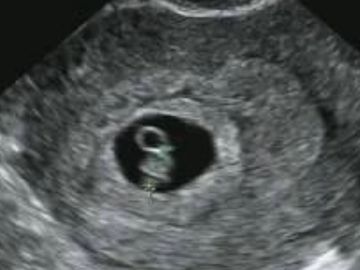

This scan is provided to confirm pregnancy, estimate the gestational age, and confirm whether it is a single or multiple pregnancy.